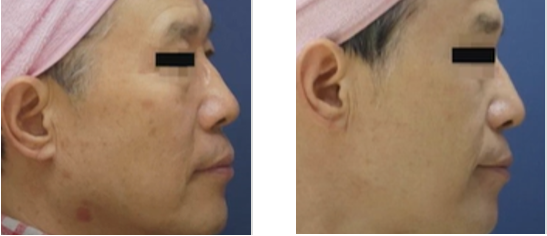

ลดความหย่อนคล้อย

ลดความหย่อนคล้อย